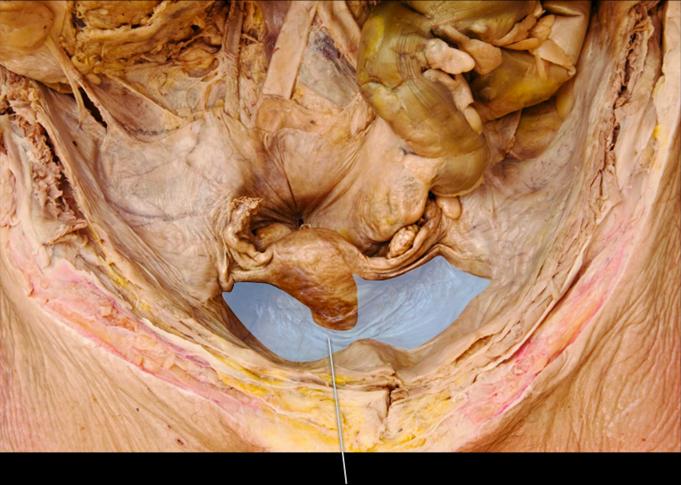

The highlighted structure is derived from which membrane?

Peritoneum

Identify the highlighted structure.

Left Uterine Tube

Identify the highlighted structure.

Ovary

Identify the highlighted structure.

Urinary Bladder